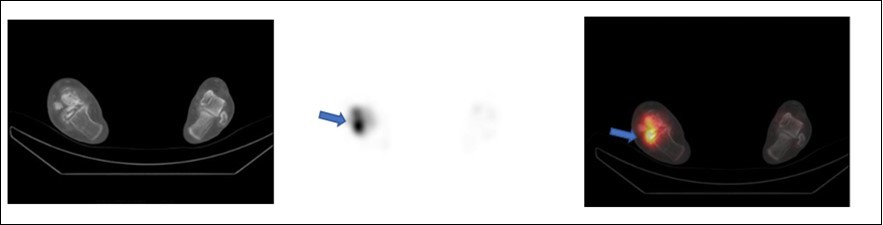

SPECT/CT depicting increased tracer uptake after one month at the site of allogenic bone grafting (same above patient) done for avascular necrosis right talus.